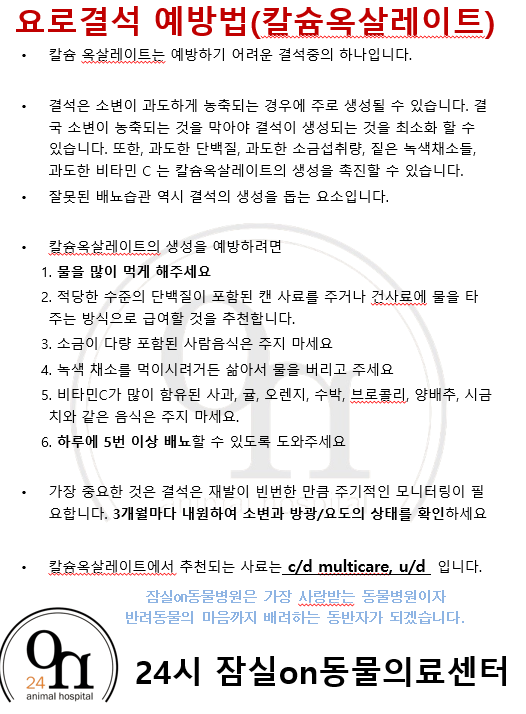

"결석성분분석을 통해

결석의 종류를 구분할 수 있습니다"

강아지에게 많이 발생하는 방광결석은

스트루바이트와 칼륨 옥살레이트 결석인데요.

칼륨 옥살레이트는 칼슘, 소금이 많은 음식 등

스트루바이트는 고단백식이나 무기질

등의 식이를 과량 급여하시게되면

발생하기 쉬워지게됩니다.

결석 제거 후

결석성분검사를 통해

해당 결석에 대한

식이조절이 함께 진행됩니다.

결석은

재발의 가능성이 있어

평소 식이조절과 음수량 등을

신경써주시는 것이 좋습니다

결석 치료 후에는

재발의 가능성이 있어

지속적인 관리가 반드시 필요하며

결석성분검사를 통해

결석의 종류에 따라

식이조절과 평소 물을 많이 먹어

배뇨를 많이 할 수 있도록

도와주시는 것이 좋습니다 :)

말티즈 친구의 제거된 결석의 모습입니다.

말티즈 아이의 결석성분분석결과

칼슘옥살레이트로

칼륨옥살레이트에 해당하는

식이방법과 주의사항에 대해

보호자님께 안내해드렸습니다 :)